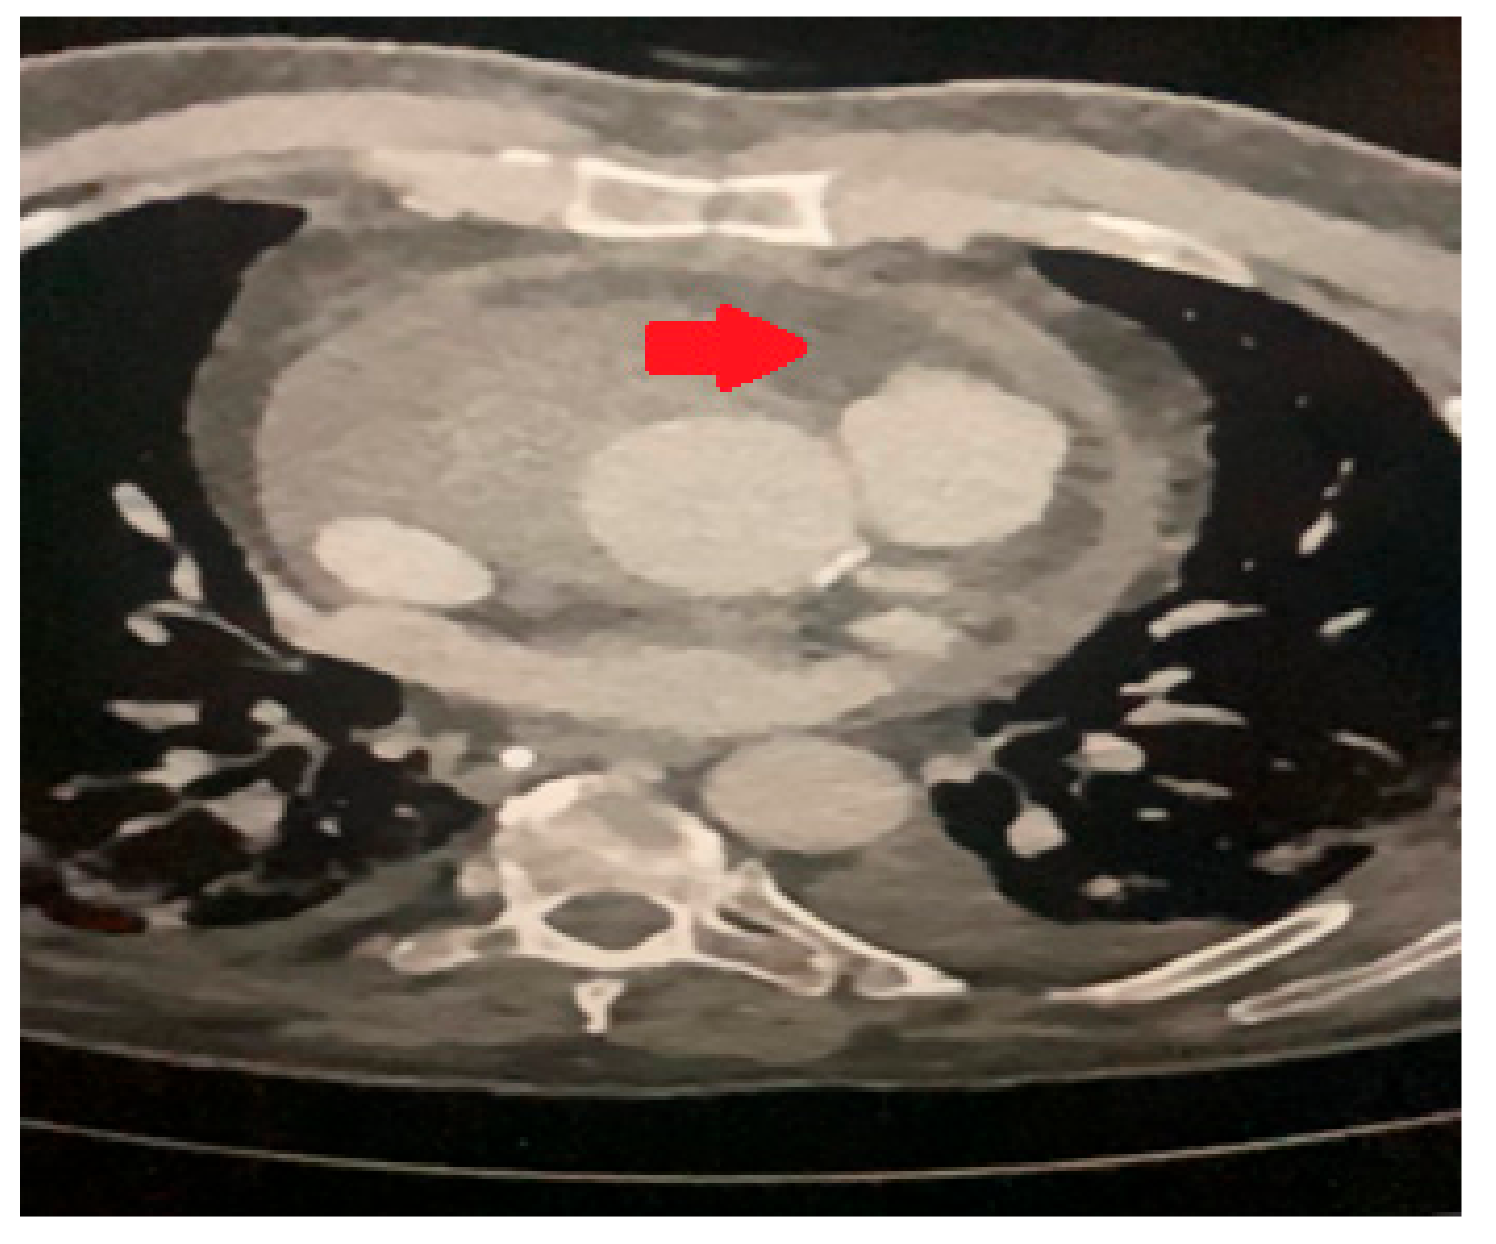

A transthoracic echocardiogram (ECHO) revealed a bicuspid aortic valve with moderate aortic stenosis (mean gradient of 28mmHg, peak gradient of 47mmHg, aortic valve area of 1.44cm2, Doppler Velocity Index =0.30cm2), moderate aortic regurgitation, and a severely dilated left ventricle with moderate systolic dysfunction (LVEF of 45%). Additionally, the aortic root and mid-ascending aorta were dilated, measuring 50mm. A computer tomography (CT) scan further confirmed the presence of aortic dilation, with specific measurements (Figure 1) showing an annulus diameter of 38 x 28mm, a sinus of Valsalva diameter of 40 x 36mm, a sino-tubular junction of 45mm, and a mid-ascending aortic dimension of 50mm. The distal ascending aorta was also 50mm, while the mid-arch measured 30mm. A CT coronary angiogram did not reveal any significant coronary artery disease.

Figure 1. Preoperative CT scan showing the dilated aortic root (arrow).